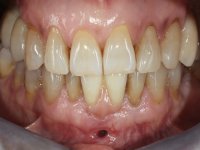

A paciente surgiu na consulta referindo que tinha aparecido um “buraquinho” na zona da gengiva junto a um implante. Não referiu ter tido dor nem qualquer tipo de tumefação.

Paciente do sexo feminino com 62 anos, fumadora. 10 Anos atrás tinha sido colocado um implante na zona dos dentes 41 e 42 para reabilitar com uma ponte de dois elementos a falta destes dois dentes. Feito o exame imagiologico foi observada uma perda óssea junto ao implante compatível com uma peri-implantite. A parede óssea vestibular junto ao implante apresentava uma extensa reabsorção, estando a superfície vestibular do implante em contacto com os tecidos moles e numa determinada zona um orifício permitia a visualização do implante através do tecido gengival. Os dentes 42 e 32 apresentavam já alguma mobilidade.